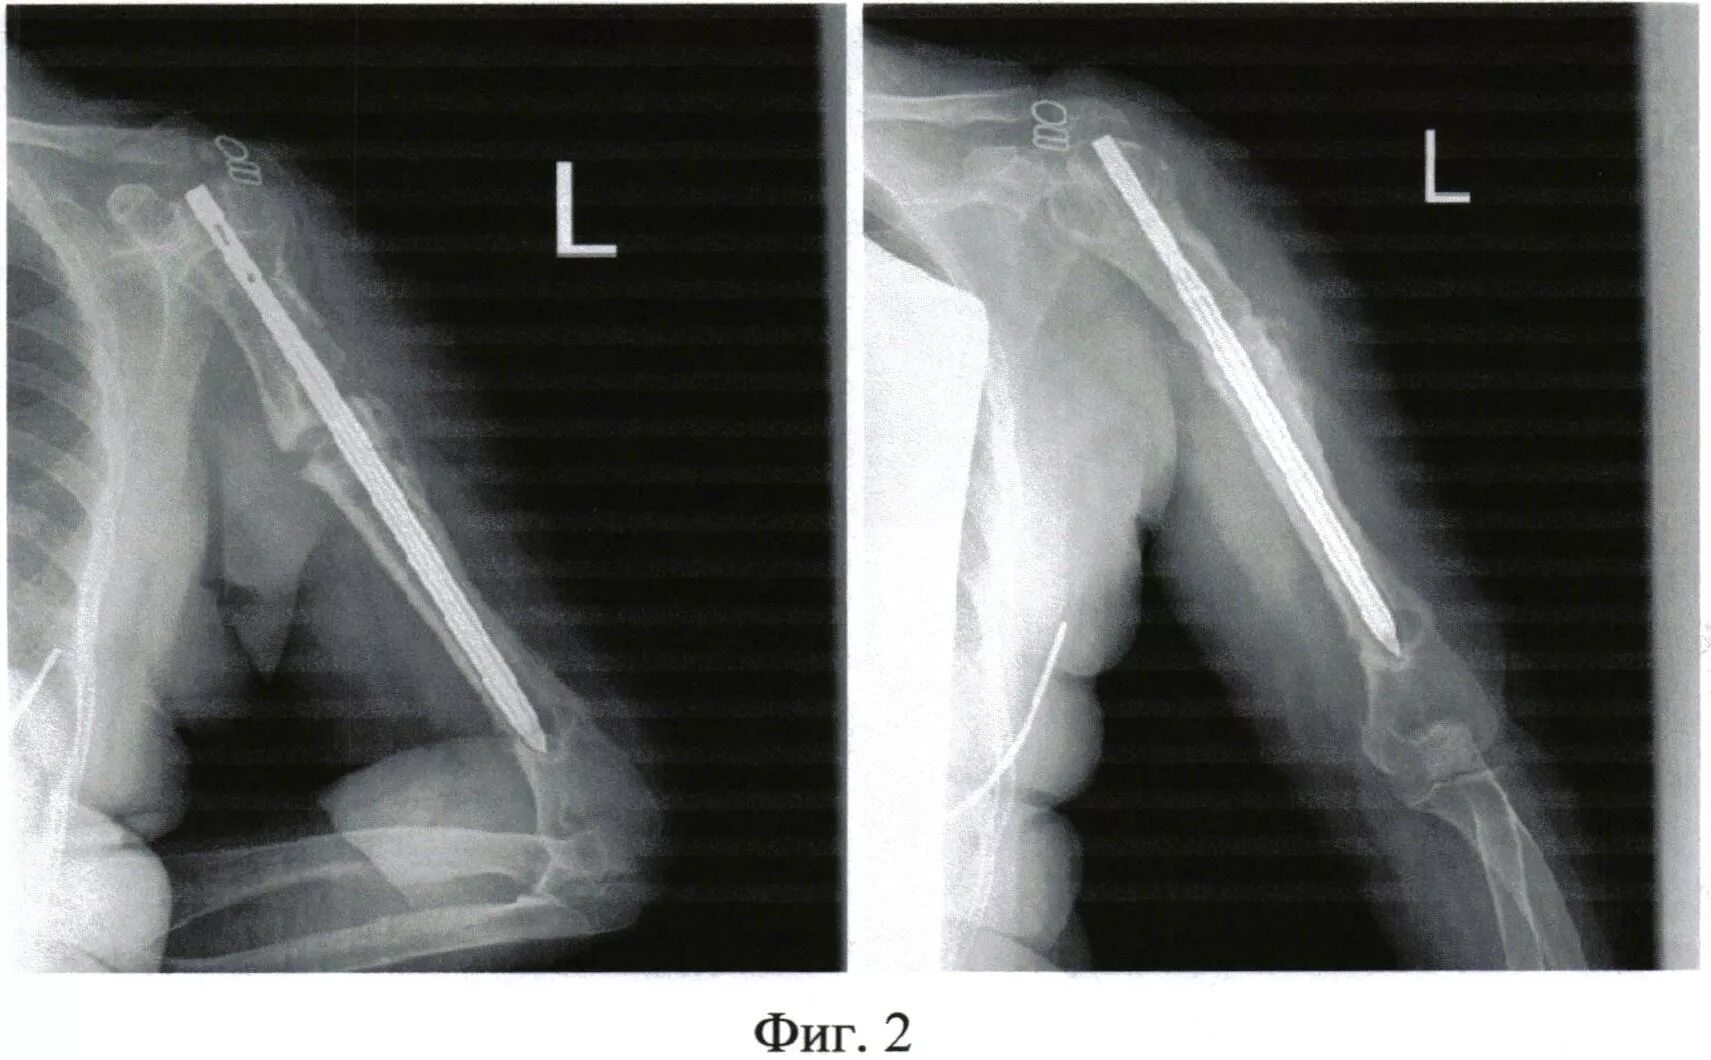

После ложных